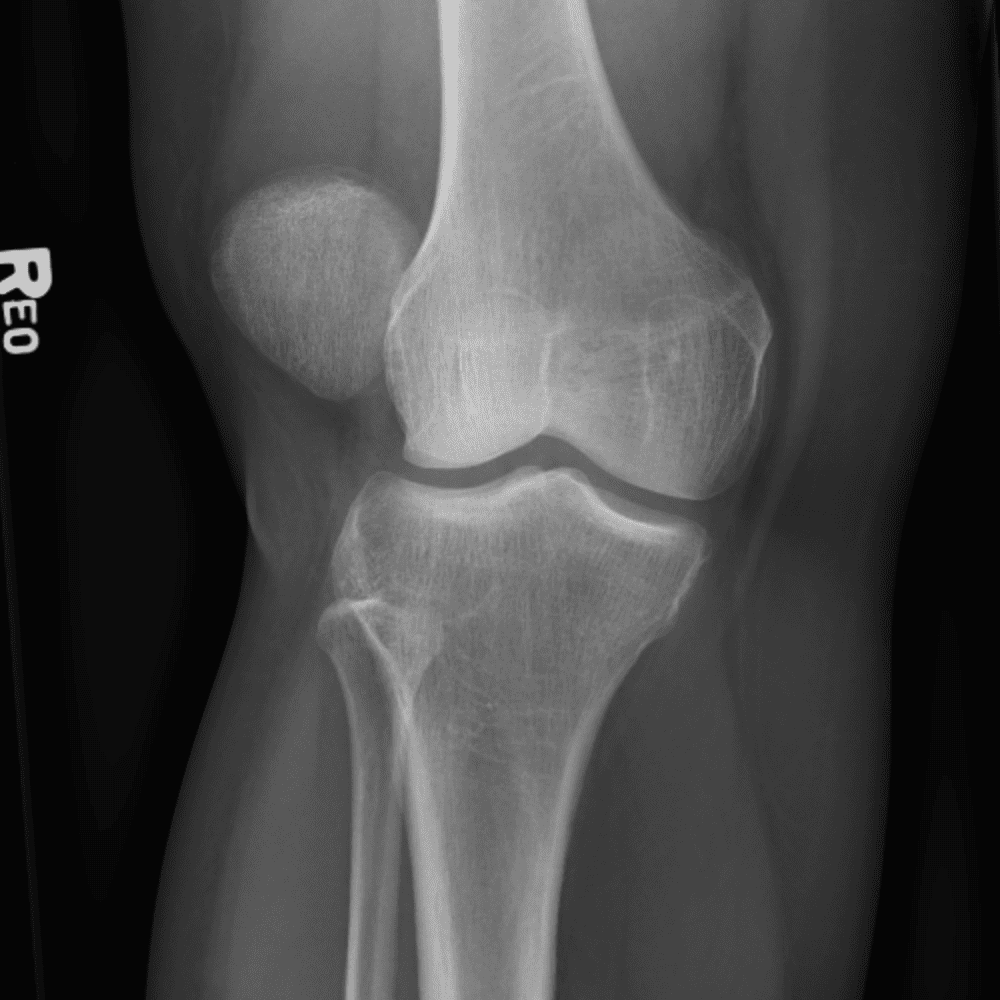

Simula o plantão incluindo casos sutis ou difíceis e alguns normais.